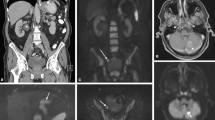

Imaging results in a 55-year-old man referred for initial staging of pancreatic cancer. PET/CT (a maximum intensity projection image, b axial PET/CT fusion) showed abnormal uptake in a large tumour of the pancreas tail (arrowhead) associated with a slight uptake in the right subdiaphragmatic area and an intense focal uptake in the pelvic area (arrows). MR-DWI (c fused T2/DWI, d DWI coronal view) also showed the pancreatic tumour (arrowhead) but identified clear perihepatic high signal (arrows) confirmed as peritoneal implants during laparoscopy

Both techniques missed PC in three patients. These false-negative results were related to subcentimetre implants in two patients and implants arising from a mucinous gastric adenocarcinoma in one patient. False-positive results were retrospectively related to small peritumoral lymph nodes that were misdiagnosed as small peritoneal implants in one patient (for both techniques). Physiological digestive uptake that had a focal appearance led to the two other false-positive results on PET. Regarding MR-DWI, a second false-positive result was retrospectively assigned to artefacts owing to the differences in susceptibility between tissue and air-filled gastrointestinal tract. Of note, one patient had ascites without evidence of PC on FDG-PET/CT and MR-DWI; pathological analysis after surgery confirmed the absence of PC.

Twenty-seven of the 90 potentially involved sites (30%) were positive for PC: inframesocolic sites (18/27), right supramesocolic sites (5/27) and left supramesocolic sites (4/27). Table 2 shows the site-based diagnostic results for the detection of PC in the 90 sites. The overall sensitivity and specificity were not statistically different between MR-DWI (74%, 97%) and PET/CT (63%, 90%, P = 0.27; Fig. 2). In the supramesocolic area, MR-DWI detected more sites than PET/CT (7/9 vs. 4/9 respectively). MR-DWI appeared especially more accurate than PET/CT in the right supramesocolic area (right supramesocolic area 5/5 vs. 3/5, left supramesocolic area 2/4 vs. 1/4, for MR-DWI and PET/CT respectively; Fig. 3). In the inframesocolic area, both techniques showed moderate sensitivities: 72% (13/18) for both techniques (Fig. 4).

Imaging results (a PET maximum intensity projection image, b PET/CT axial fusion, c fused T2/DWI) in a 65-year-old man with previously treated colon cancer with synchronous liver metastases who had increasing tumour markers. Both PET/CT (a MIP, b fused images) and MR-DWI (c fused T2/DWI) showed a focal lesion in the inframesocolic area anterior to the left psoas muscle (arrows). Surgical and histopathological findings confirmed the recurrence

Imaging results in a 57-year-old woman with a previously treated gastric cancer referred for a suspected recurrence (increased level of tumoral markers). PET/CT (a PET maximum intensity projection image) was negative, whereas MR-DWI showed high signal in the perihepatic space (b arrow). A consensus was found resulting in a “wait and see” attitude at the multidisciplinary meeting. Imaging follow-up at 3 months (c PET, d DWI) showed disseminated peritoneal lesions (arrows)

Imaging results in a 61-year-old man referred for initial staging of small-bowel cancer. PET/CT (a axial CT, b axial PET/CT fusion) showed a slight pathological uptake on pericolic subcentimetre nodules (arrows). MR-DWI (c axial T2, d axial DWI) showed moderate pericolic ascites but without high signal on DWI. Diffuse peritoneal implants were confirmed during laparoscopy